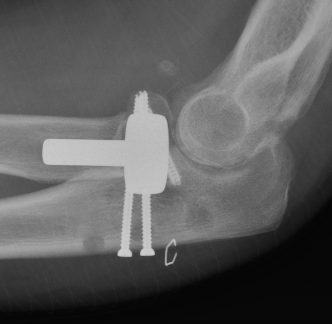

Medial approach and screw fixation